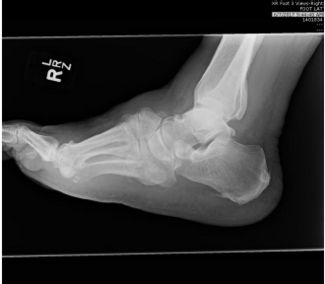

In this video, Dr. Abicht dives into key components of radiographic assessments.